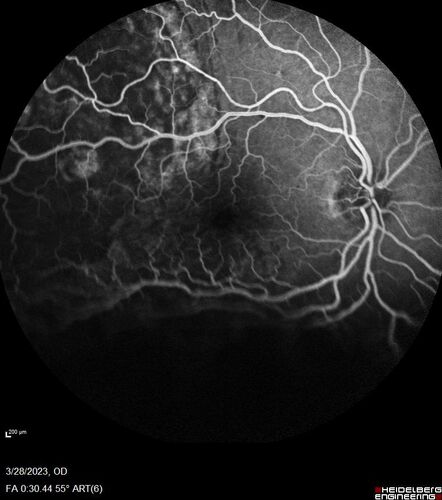

Choroidal Metastatic Breast Cancer with Exudative Detachment

58 year old female presented with 20/200 vision. Had 10 sessions of radiation and tumor shrank. The exudative detachment took almost a year to resolve. The vision improved to 20/40.